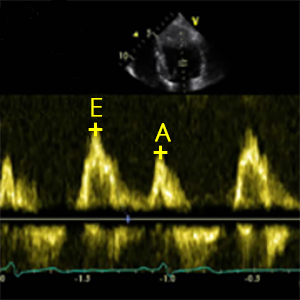

Na ehokardiogramu, pacijenti sa IR su imali značajno veći indeks mase leve komore (79 prema 68 g/m2), end-dijastolni volumen leve komore (87 naspram 75 mL) i end-sistolni volumen leve komore (32 prema 27 mL). IR i non-IR grupe nisu se razlikovale u smislu indeksiranog volumena leve pretkomore, brzine protoka preko mitralnog ušća merene u ranoj dijastoli (E), brzine protoka preko mitralnog ušća merene u kasnoj dijastoli (A) ili srednje medijalne brzine septalnog mitralnog anulusa (e′). Međutim, pacijenti sa IR imali su značajno niži mitralni E/A odnos (0,944 naspram 1,298), što je verovatni pokazatelj pogoršane dijastolne funkcije.

Čini se da insulinska rezistencija ubrzava obrazac tipičnih promena na srcu kod pacijenata sa dijabetesom tipa 1. U poređenju sa učesnicima bez insulinske rezistencije, pacijenti sa dijabetesom tipa 1 i insulinskom rezistencijom imali su značajno pogoršan mitralni E/A odnos i izrazito pogoršane brzine mitralnog anulusa. Insulinska rezistencija je u pozitivnoj korelaciji sa mitralnim E/A odnosom u podgrupi pacijenata sa prekomernom težinom, dok ta korelacija nije nađena u grupi sa normalnom težinom i u grupi gojaznih pacijenata, za šta nije nađeno validno objašnjenje. Odnos zapremine leve komore i leve pretkomore (LVLAVR), nov i još uvek nevalidiran indeks, izgleda da može da se koristi za stratifikovanje pacijenata u podgrupe sa specifičnim rizikom od neželjenih srčanih ishoda. Međutim, potrebne su dalje analize da bi se potvrdila ova premisa.